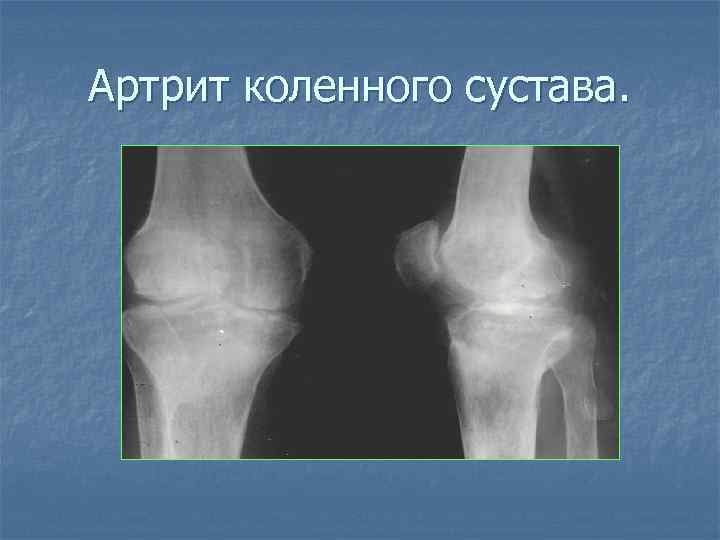

Артрит коленного сустава.